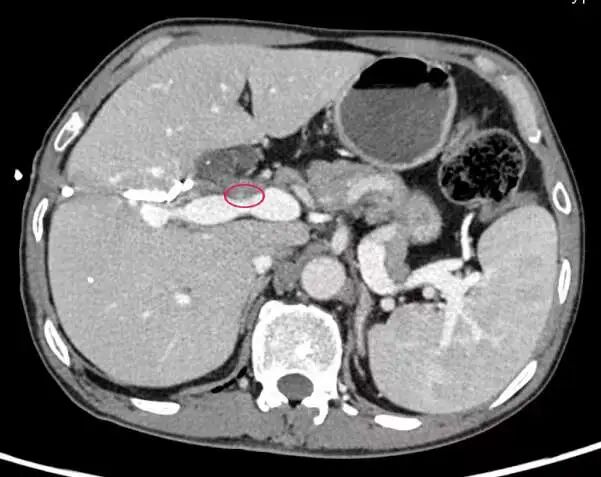

近日,四川大学华西医院胆道外科程南生、李富宇教授团队为一例胆囊癌累及血管、胆管的患者,成功实施了包含肝切除术、胆管分叉切除、门静脉切除重建、肝右动脉修补、扩大淋巴结清扫、多支胆管吻合在内的腹腔镜胆囊癌扩大根治术。 经文献检索,国内外未见胆囊癌患者在腹腔镜下实施包含门静脉切除重建在内的胆囊癌扩大根治术的相关报道。 老赵(化名)平时在工地上打零工,3个月前,老赵觉得上腹胃这个部位开始不舒服,连忙去卫生院检查,被告知没得胃病是胆囊结石,开了点消炎利胆的药吃了几天就感觉好点了。 但是一个月过会,老赵的眼睛、全身皮肤逐渐开始发黄,皮肤瘙痒,上腹部又感觉隐痛不适,吃饭后腹胀,大小便颜色都不正常了,小便就像浓茶、大便就像陶土。老赵以为自己发了肝炎或者什么传染病,赶紧到当地人民医院看病,CT、MRI等等检查都做了,最后被婉转地告知得了胆囊癌。 家人四处打听,老赵辗转了多家医院后来到华西医院胆道外科程南生、李富宇教授团队处就诊。 胆囊位于右上腹肋骨下,主要作用是贮存肝脏分泌的胆汁,也就是所谓的“苦胆”,当进食时诱发胆囊收缩,胆汁排入肠道帮助消化食物,“让我们吃饭更香”。 胆囊癌是消化系统第五大恶性肿瘤,是胆道系统最常见的恶性肿瘤。早期胆囊癌临床症状不明显,仅有右上腹部不适、疼痛等类似胆囊结石症状,肿瘤侵犯胆管后眼睛和皮肤会变黄,肝功严重受损,如不及时诊治,会导致肝功衰竭危及生命。 发病率“高” 近年来,世界范围内胆道肿瘤的发病率逐渐增加,我国的胆囊结石患病率已与欧美接近,胆囊癌发病率也随之增加。 发现“难” 胆囊癌起病隐匿,临床症状不明显,早期多数患者没有临床症状,仅有右上腹部不适、疼痛等类似胆囊结石症状。多数胆囊癌患者在诊断时已属进展期或晚期,部分病例丧失手术机会,如何提高进展期胆囊癌的切除率至今仍是胆道外科中的难点与重点。 根治“难” 此外,胆囊癌切除率低和预后较差的另一个重要原因在于肿瘤侵袭性强,容易发生毗邻脏器和血管的侵犯。胆囊颈部和胆管的后方就是门静脉和右肝动脉,进展期胆囊癌极易侵犯临近的胆管、肝动脉、门静脉、胃窦、结肠、胰头等部位,该部分病例需进行包含联合脏器切除或血管切除的扩大切除才能获得根治性切除,手术难度大、切除率较低。 然而,包含血管切除重建在内的根治术目前仍是胆囊癌患者获得长期生存的主要治疗手段。 老赵的胆囊癌已经累及血管、胆管,术前眼睛和皮肤发黄,食欲体重下降明显。胆囊癌对药物治疗不敏感,如不实行手术,他的生存期一般仅半年至一年。综合考虑过后,程南生、李富宇教授团队决定为老赵行腹腔镜胆囊癌扩大根治术。 术前CT显示肿瘤位置 由于老赵存在胆管梗阻,术前手术团队为他先做了胆道穿刺引流改善肝功至正常,合并营养改善后才正式实施手术。 术中见肿瘤不仅侵犯和阻塞肝脏胆汁分泌的主要流出道-胆管,更糟糕的是还多处侵犯了肝脏血液供应的主要流入道—门静脉主干、门静脉右支起始部,并致密包饶了肝脏血液供应的另一主要血管—肝右动脉。 如果不能切除肿瘤受累的血管并成功重建肝脏的主要供血血管-门静脉,只能放弃根治性切除手术,老赵的生存期将会很短。 对此,手术团队在腹腔镜下分别分离出和阻断门静脉左支、右支和主干,切除门静脉受累部分,在肝门狭窄的空间内成功完成腹腔镜下门静脉重建。 肿瘤在侵犯胆管、门静脉的同时,360度致密包饶肝右动脉。 虽然老赵的胆管梗阻经过术前胆道穿刺引流改善肝功,但胆汁性肝硬化严重,无法耐受扩大右半肝切除,而肝右动脉如无法在腹腔镜下从肿瘤中剥离出来只能放弃根治术。 团队在术中经腹腔镜下仔细解剖分离,采用打开肝动脉血管外鞘膜技术,发现肝右动脉并未受侵犯,将肝右动脉从肿瘤包饶中艰难剥离出来,在腹腔镜下修补多处肝动脉破口。 腹腔镜下切除肝门部胆管分叉后,再进行多支细小胆管断端的胆肠吻合。 由于解剖关系或肿瘤侵犯,胆道肿瘤多数需要附加大范围的肝切除、规范的淋巴结清扫、精准的胆肠吻合术、血管切除重建或联合脏器切除,因而手术更为复杂和耗时。 目前国内外常规开展胆囊癌腹腔镜根治术的单位极少,未见胆囊癌患者在腹腔镜下行门静脉切除重建、肝动脉修补的相关扩大根治术文献报道。我院胆道外科程南生、李富宇教授团队在前期胆囊癌腹腔镜联合脏器切除和再次手术根治的经验基础上,完成了该例包含血管切除重建在内的腹腔镜胆囊癌扩大根治术。 术中严格遵循无瘤原则,腹腔镜血管切除重建达到了开腹手术的解剖标准,在保障患者远期疗效的前提下,术后运用加速康复外科理念,老赵术后恢复速度明显快于传统开腹手术。 出院的时候,老赵说,“我无法用言语来表达我的谢意和敬意,医生护士们说我听话好好康复、好好生活就是对他们最大的表扬!” 腹腔镜根治性术已经广泛应用在胃肠、肝脏和胰腺肿瘤,并且成为了常规术式之一,但腹腔镜胆道肿瘤目前在世界范围内均刚起步。特别是像腹腔镜胆囊癌根治术这种复杂耗时的手术,国内外开展的单位极少,但技术的进步和发展趋势是必然和必须的,也是外科医生的追求和职责所在。 胆道外科程南生、李富宇教授团队从2015年开始率先探讨腹腔镜胆囊癌根治术,初期无经验可借鉴,在华西“精业、创新”文化底蕴的支撑下,聚焦胆道肿瘤的微创外科的发展方向,严格遵循国际指南和当前技术难点,制定并实施了一系列规范化的诊治和手术流程、不断优化手术步骤与改进技术,进展期胆囊癌的切除率和微创完成比例明显提升。 目前团队完成的胆囊癌再次腹腔镜根治术例数、T3期胆囊癌腔镜扩大根治术例数均系国际单中心例数最多的团队之一;完成的胆道探查术后、联合多脏器切除的腹腔镜胆囊癌再次扩大根治在国际上均未见相关报道。他们的系列探索有助于改变目前进展期胆囊癌无法在腹腔镜下完成联合脏器和血管切除的传统观念,有助于改善目前国际上胆道肿瘤微创化起步晚、进展缓慢和微创手术适应症窄的局面。 精业、创新,华西人永远在路上!